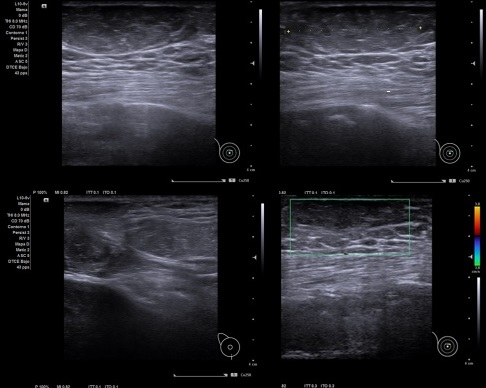

Caso 2: Se aprecia exoestructura compatible con lipoma… No captación Doppler. Bien delimitado, de unos 20 mm de diámetro mayor.

Caso 2: Lipoma en piel de mama.

Diagnóstico diferencial: Masa de origen mamario.